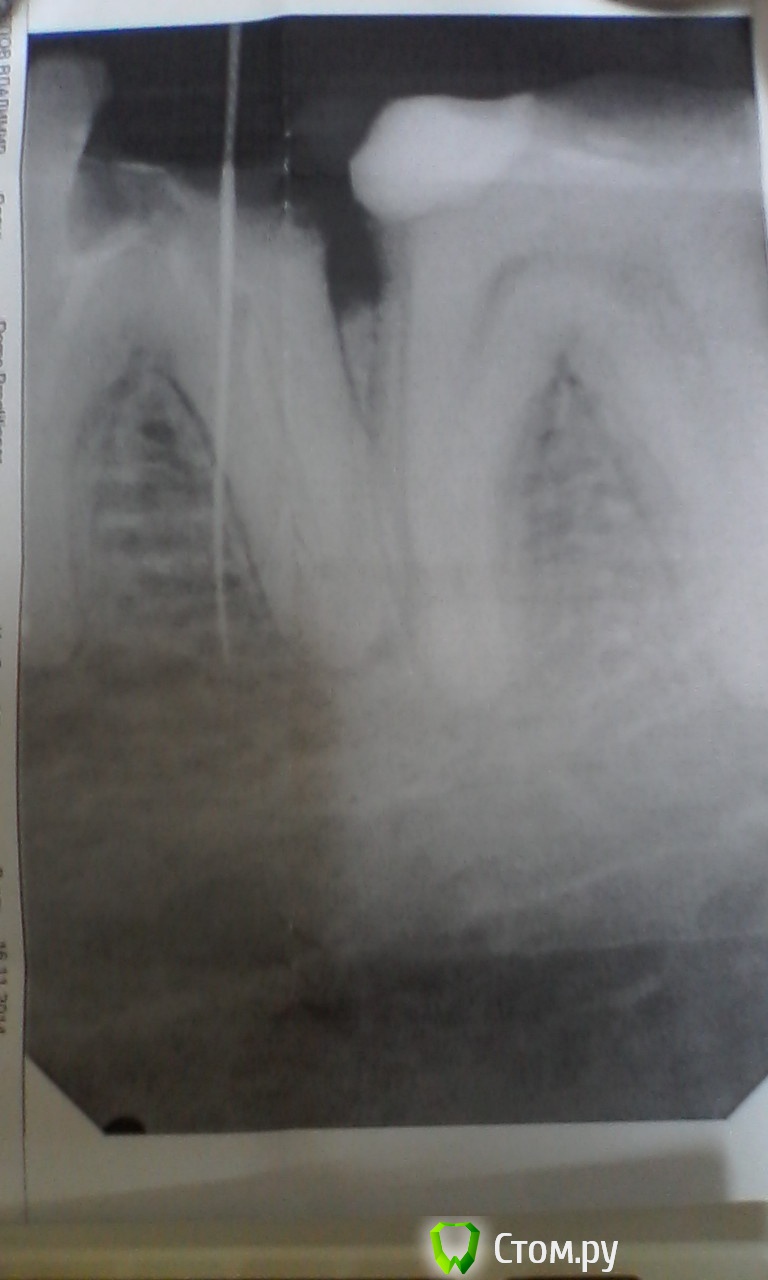

Vladimir_1 Опубликовано 18 ноября, 2014 Поделиться Опубликовано 18 ноября, 2014 У меня сложилась очень плохая ситуация ( даже не знаю что делать...В общем молодой врач мне готовил зуб под вкладку. И не верно прошёл в канал зуба (см. фото. на нём видна иголка). У меня к Вам несколько вопросов помогите разобраться.Скажите этот зуб вообще можно было делать для установления коронки ? Ортопед или терапевт должен был определить можно его делать или нет ? И что мне сейчас делать ? виноват врач ? и можно ли это исправить ? ходил к другому терапевту в той же клинике и она отказалась его готовить для коронки (или просто не захотела брать ответственность на себя после неудачной попытки ?)Вообще его возьмуться повторно сделать или нет ? я уже плачу с этими зубами... не знаю куда кидаться Спасибо !!! очень на Вас надеюсь Ссылка на комментарий